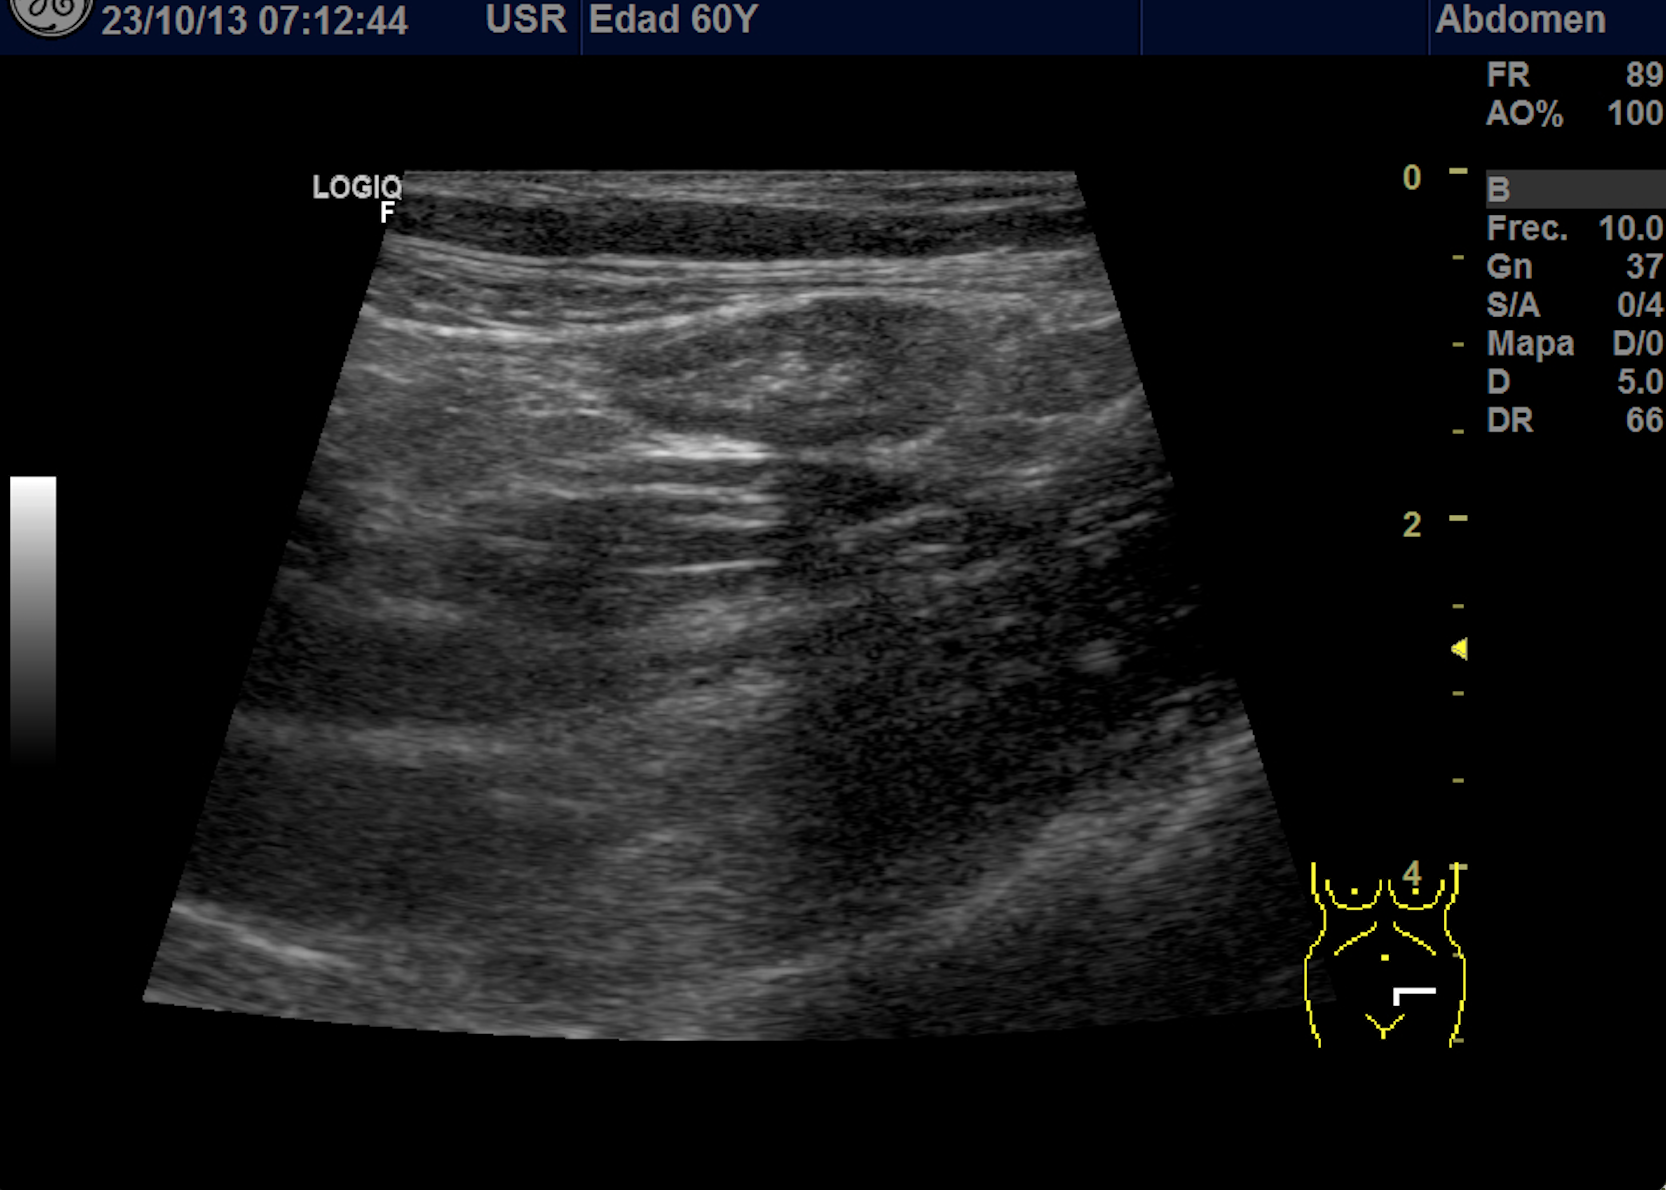

Se explora FII-hipogastrio y en el punto de más dolor se observa engrosamiento de asas de intestino grueso sin peristaltismo y con signos de edema de la grasa adyacente. No líquido libre.

También se realiza ecografia en urgencias del hospital.

En el hospital se realiza una nueva ecografía en el servicio de radiología confirmando el diagnóstico de sospecha: diverticulitis aguda en sigma distal sin datos de complicación. Hinchey 1A.